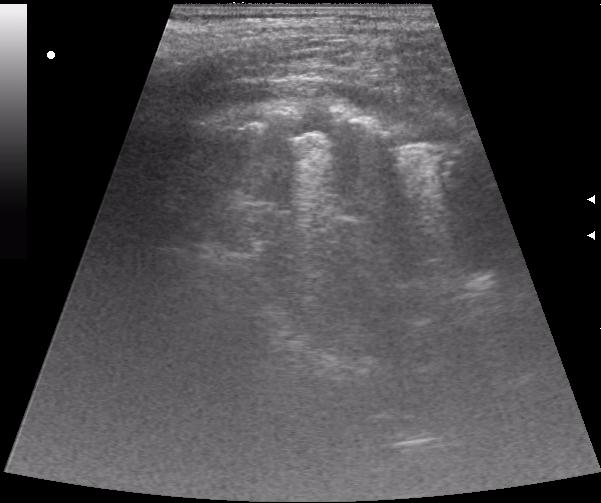

после